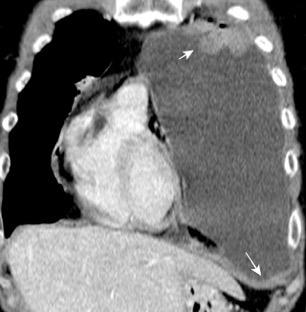

La ocupación del espacio pleural por derrame (o obstrucción aérea) se acomoda con expansión aumentada de la caja torácica, especialmente en eje vertical. La consecuencia es aplanamiento e incluso inversión diafragmática.

Afzal S, Fatima K, Ambareen M. Antenatal ultrasound diagnosis of congenital high airway obstruction syndrome: a case report and review of literature. Cureus. 2019. Thoma R et al. Physiology of breathlessness associated with pleural effusions. Curr Opin Pulm Med. 2015

Wang JS et al. Changes in pulmonary mechanics and gas exchange after thoracentesis on patients with inversion of a hemidiaphragm secondary to large pleural effusion . Chest 1995

Mesotelioma epitelioide